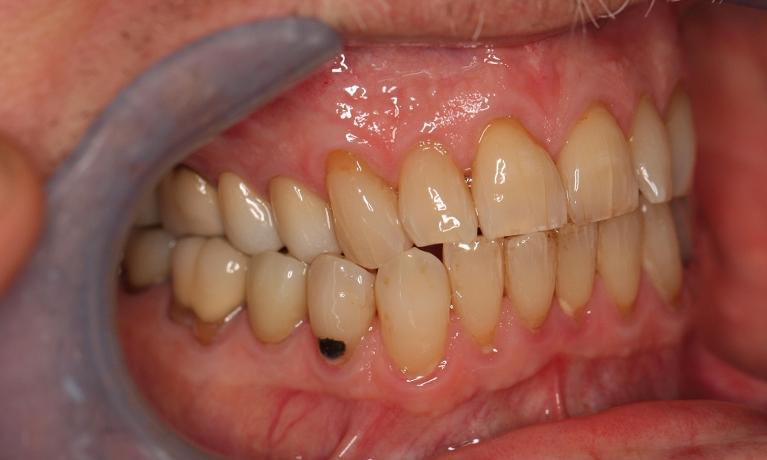

This man in his 50s was unhappy with the amalgam filling used to fix cavities. After discussing options, we agreed to fix his appearance by putting crowns on the teeth which create more of a natural look. This patient was very happy with the end result and is now in maintenance mode.